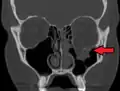

Zlomenina spodiny očnice (blow-out fracture) -